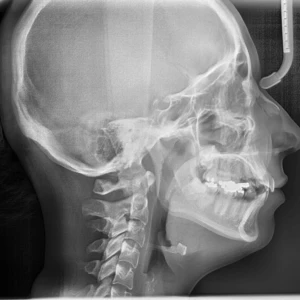

Giới thiệu chỉnh nha Khớp cắn được định nghĩa đúng là “môi trường trung gian mang tất cả những chuyên ngành của nha khoa lại với nhau” – theo Ramford và Ash. Ricketts Dorlands. Từ điển y khoa định nghĩa khớp cắn là “quá trình đóng hàm”. Trong nha khoa, khớp cắn được xem là “tương quan giữa các răng hàm trên và hàm dưới khi chúng tiếp xúc chức năng với nhau trong suốt quá trình hoạt động của hàm dưới”.

Nghiên cứu về Giới thiệu chỉnh nha khớp cắn liên quan đến toàn bộ hệ thống nhai, hiểu được mối liên hệ lẫn nhau giữa răng, mô nha chu, xương, khớp, cơ và hệ thống thần kinh trong khi hàm dưới di chuyển, cũng như là khi thực hiện chức năng bình thường. Nghiên cứu khớp cắn là điều cần thiết để thấu hiểu và đạt được những mục tiêu khi điều trị chỉnh nha.

Thế nào được xem là khớp cắn bình thường trong chỉnh nha, hay là khớp cắn hạng I Angle. Răng chìa khoá trong phân loại này là răng cối lớn vĩnh viễn thứ nhất. Múi ngoài gần của răng cối lớn thứ nhất hàm trên khớp vào rãnh ngoài gần của răng cối lớn vĩnh viễn thứ nhất hàm dưới. Tuy nhiên, thậm chí với tương quan này, khi răng đầy đủ thì vẫn có sự bất hài hoà giữa tương quan hàm dưới hoặc khớp thái dương hàm với hàm trên.

Khớp cắn bình thường thường liên quan đến tiếp xúc mặt nhai, sự sắp xếp của các răng, cắn chìa, cắn phủ, sự sắp xếp và tương quan răng giữa các cung hàm và tương quan giữa răng với cấu trúc xương.